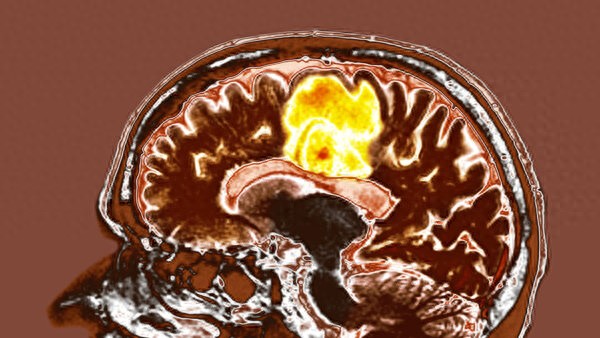

胶质母细胞瘤是一种侵袭性极强的 癌症,但一项针对两种常见补充剂对胶质母细胞瘤肿瘤进行测试的新研究取得了令人鼓舞的结果,这可能为治疗这种疾病提供一种新的方法。

鉴于胶质母细胞瘤的生存率很低,科学家们正在努力寻找新的、改进的方法来对抗这些肿瘤,而这项研究可能提供另一个探索的途径。